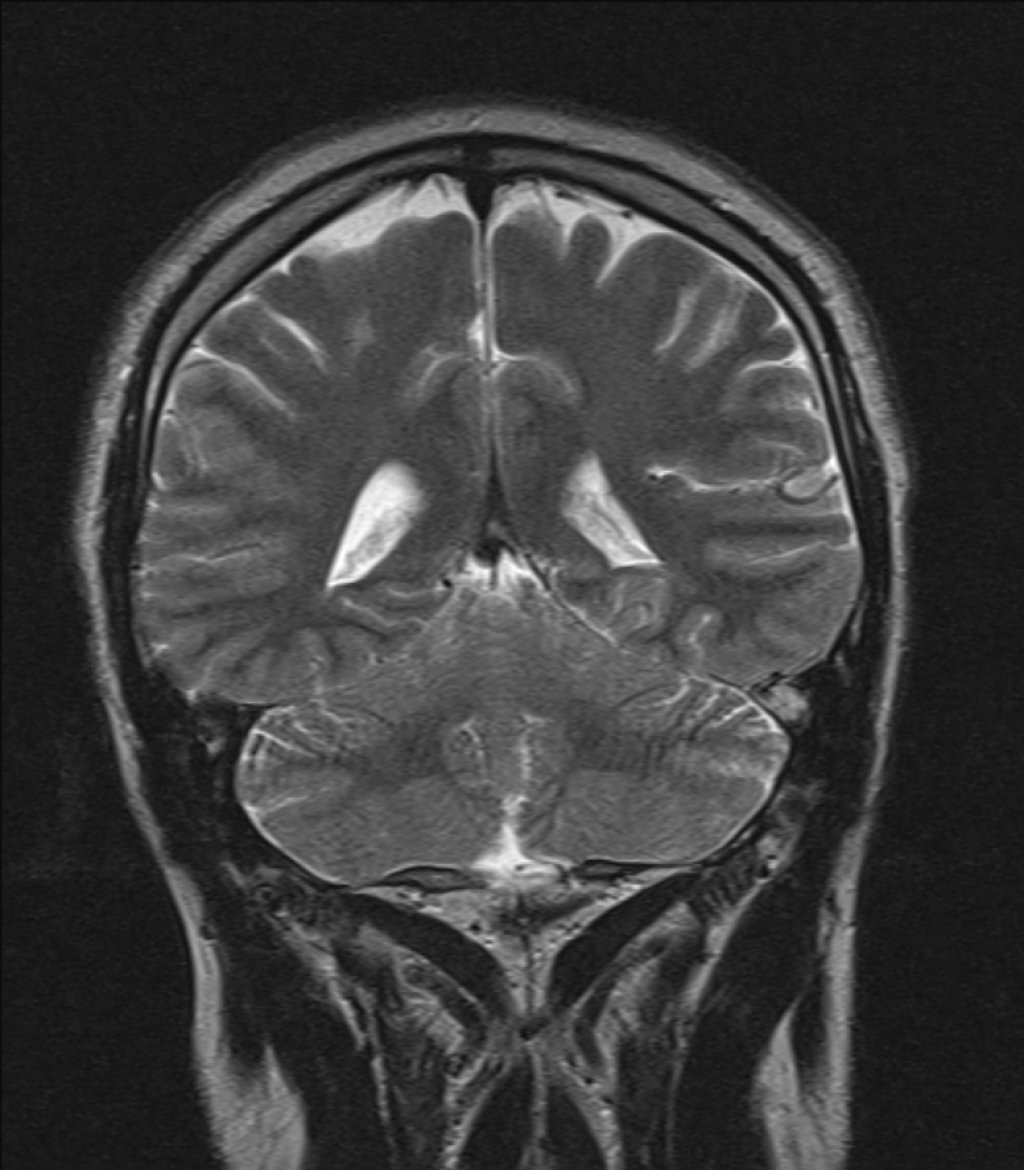

- Магнитно-резонансная томография (МРТ) головного мозга: позволяет получить детальные изображения структур мозга, выявить возможные структурные аномалии или очаги поражения, которые могут быть связаны с эпилепсией.

Каллозотомия (КЗ) — это хирургическая процедура, в ходе которой частично или полностью рассекается мозолистое тело. Мозолистое тело представляет собой крупный пучок нервных волокон, соединяющий два полушария головного мозга. Его основная функция — обеспечение связи и координации между левым и правым полушариями. При некоторых формах эпилепсии, особенно тех, которые сопровождаются генерализованными приступами, эпилептическая активность быстро распространяется из одного полушария в другое именно через мозолистое тело. Рассечение этих волокон прерывает пути распространения патологической электрической активности, что помогает снизить частоту и тяжесть приступов.